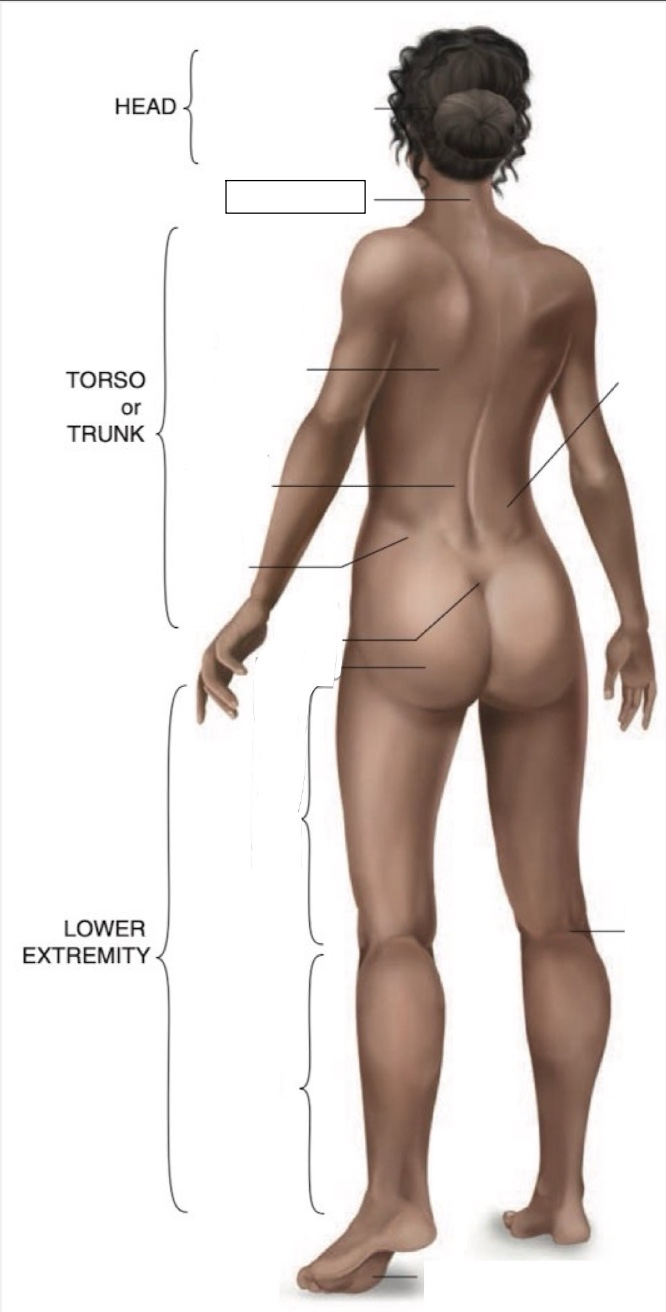

Occipital region

Cervical region

Inferior angle of scapula

Lumbar region

Iliac crest

Sacral region

Buttock

Flank